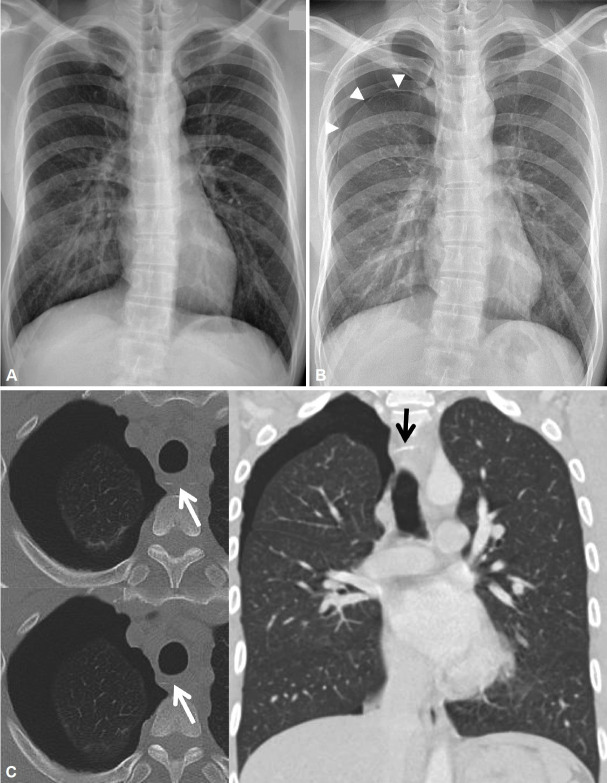

Although most digestive tract foreign bodies pass naturally, approximately 10% require endoscopic removal and another 1% require surgical intervention. The upper esophagus is the most common site of foreign body impaction. In the East, fish bones are the most commonly encountered foreign bodies in the esophagus, whereas in the West, meat is the most common. Prompt removal of these impacted foreign bodies is important because they may lead to serious complications, such as esophageal perforation or obstruction. The esophagus is located in the deepest part of the chest and is in close proximity to vital organs, such as the aorta, heart, lungs, and vena cava. Thus, a sharp foreign body that penetrates the esophagus may puncture nearby organs, potentially leading to a variety of intrathoracic organ complications, including an aortoesophageal fistula, pericarditis, and pneumothorax. Although pneumothorax rarely results from fish bones impacted in the esophagus, we report two cases of characteristic pneumothorax caused by fish bone foreign bodies in the esophagus and provide a review of the associated literature.